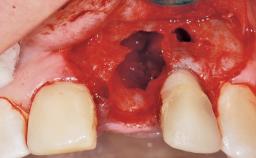

A 30-year-old female patient had lost tooth 21 and was referred to our clinic for consultation and treatment. Due to advanced apical infection, tooth 21 had been extracted two months earlier at another clinic and an acrylic-resin tooth had been bonded to the adjacent teeth. The patient desired implant treatment to avoid any damage to the adjacent natural teeth. While the patient had no history of any systemic disorder, she was a heavy smoker and exhibited medium to advanced periodontitis in the entire jaw. After the initial treatment to achieve a pocket probing depth of less than 4 mm and no bleeding on probing, a decrease in the height of the papillae mesial and distal to the extraction site and overall gingival recession were observed.

| Bone Augmentation | Horizontal|Staged |

| Augmentation Materials | Autogenous chips|Membrane |

| Soft Tissue Grafting | Simultaneous |

| Bone Volume | Deficient horizontally, requiring prior grafting |